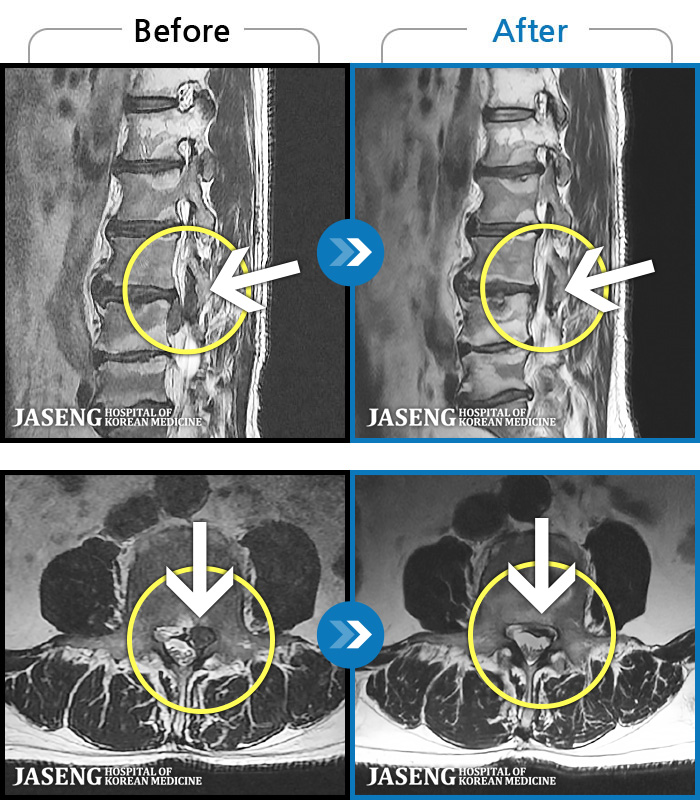

MRI ġ

MRI ũ ʸ Ȯϼ.